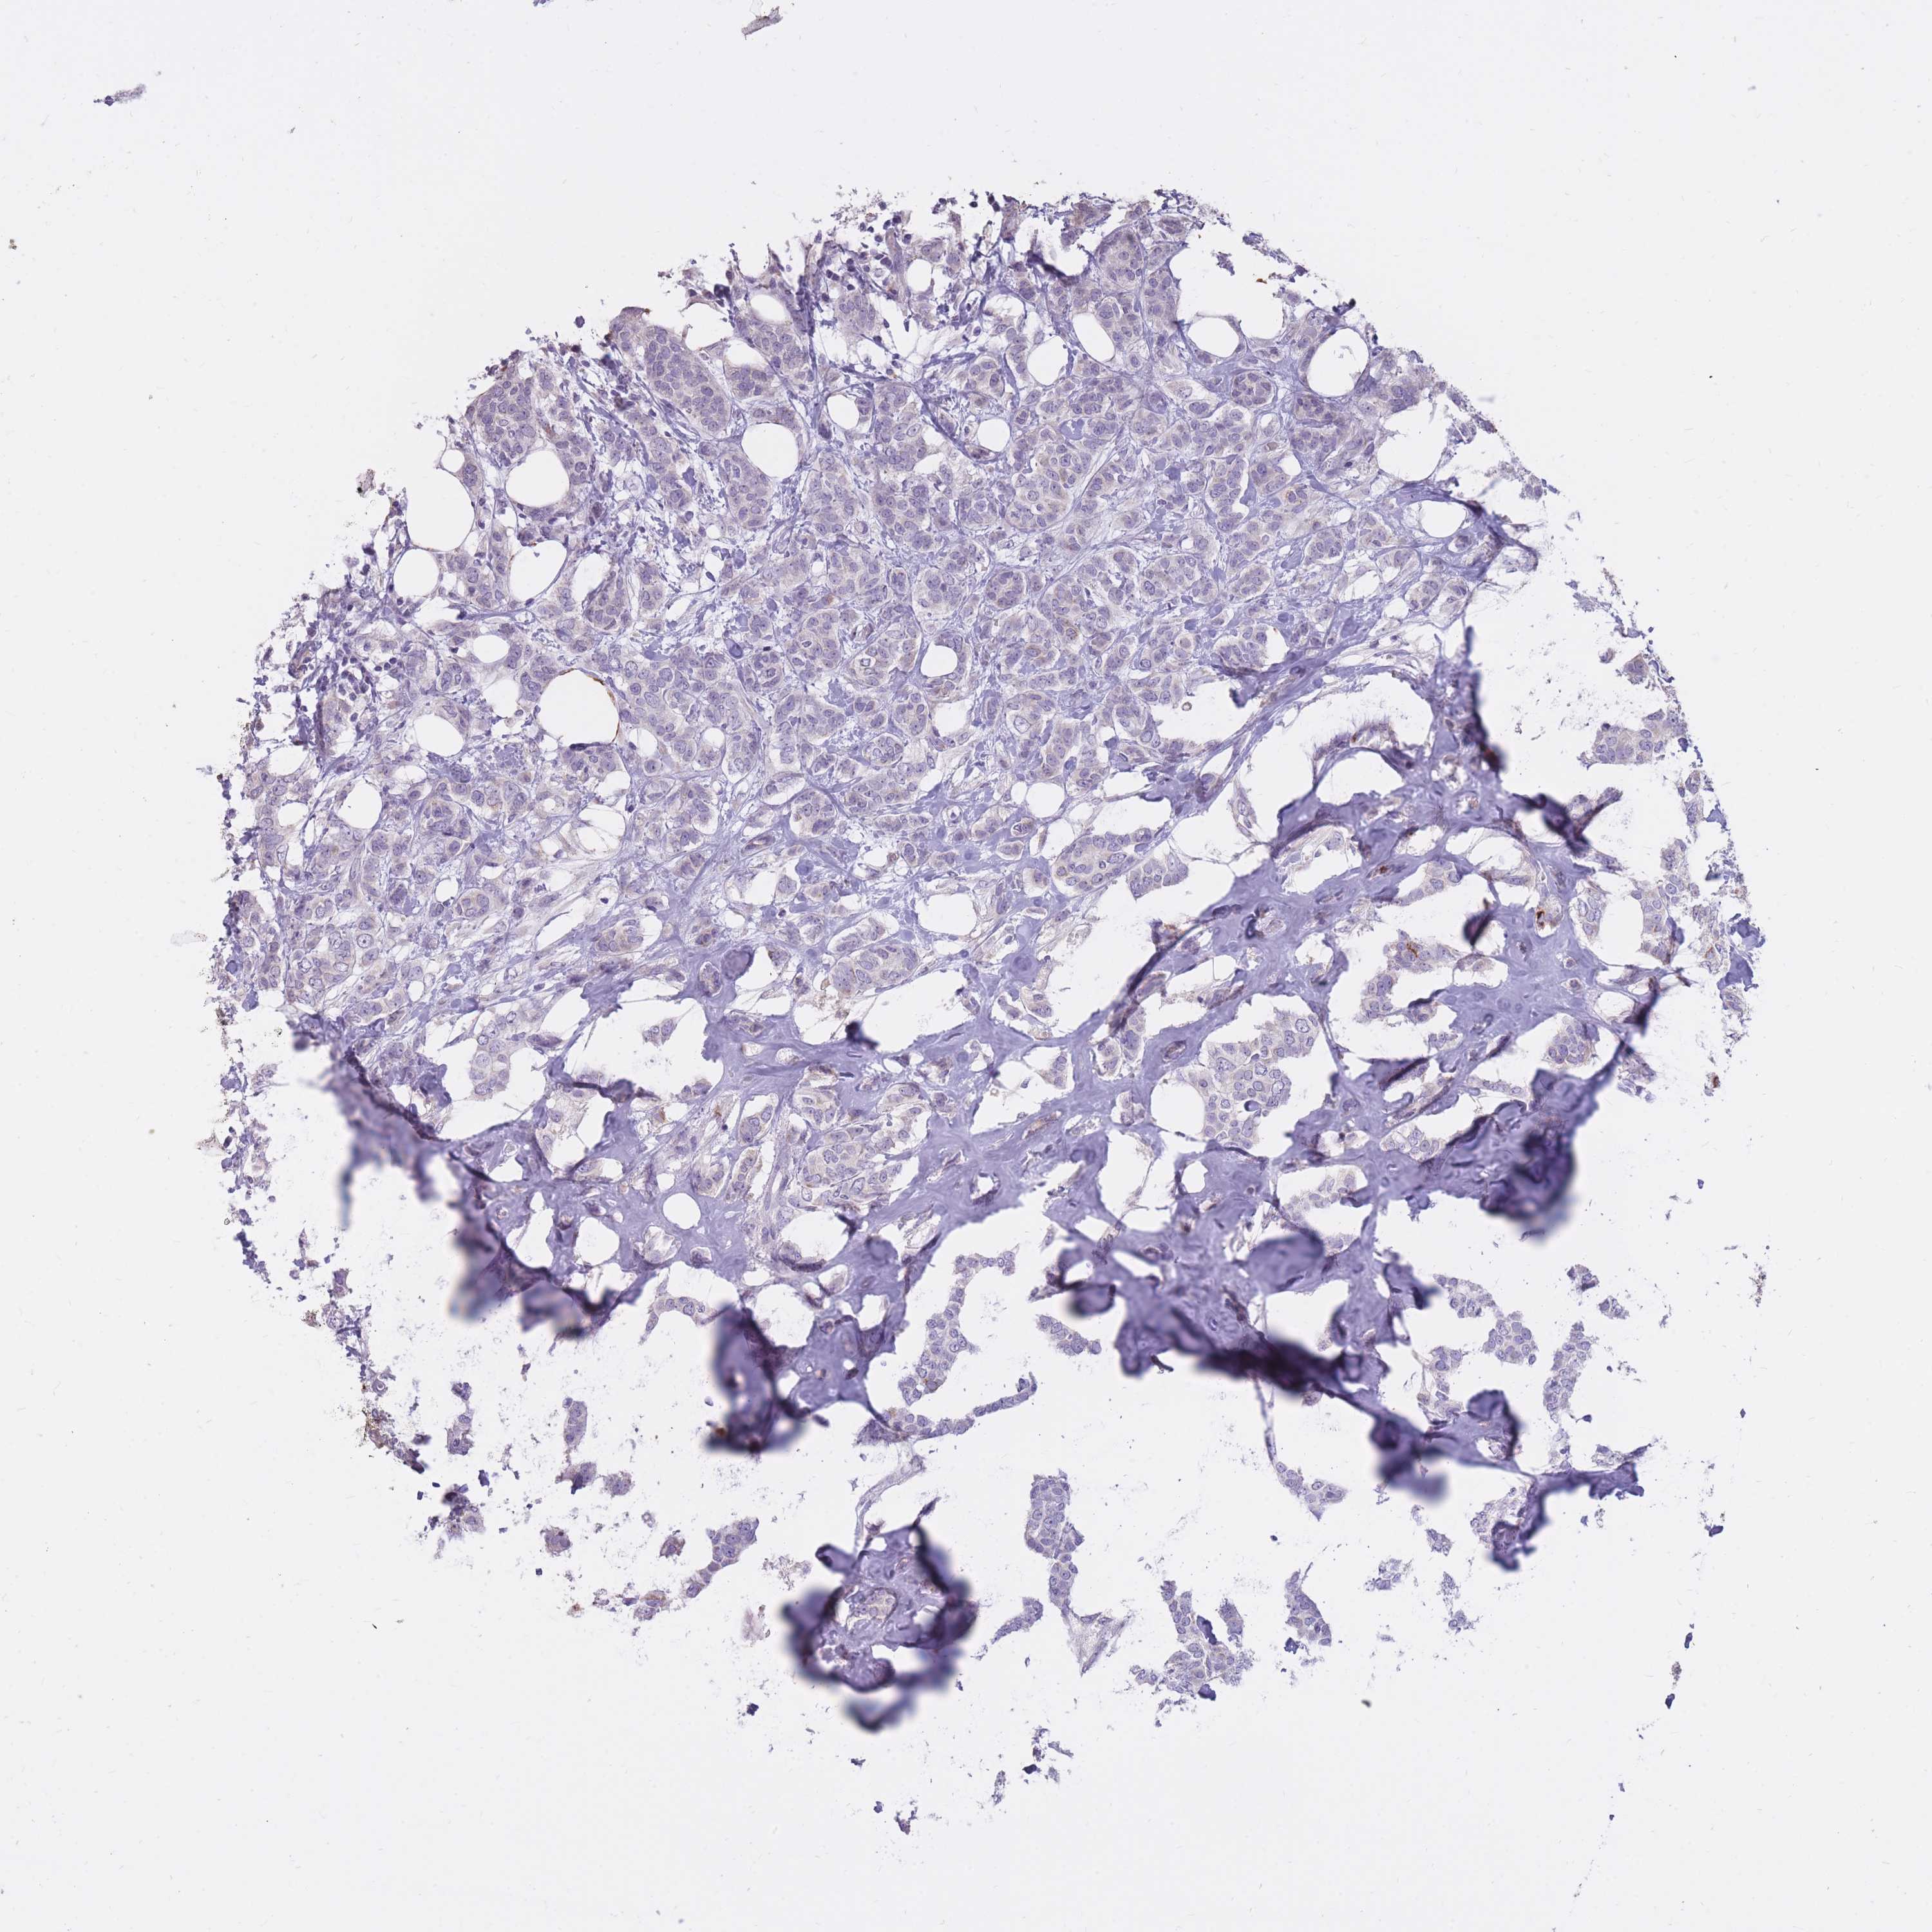

BRCA TCGA BRCA VALIDATION PROTEIN EXPRESSION